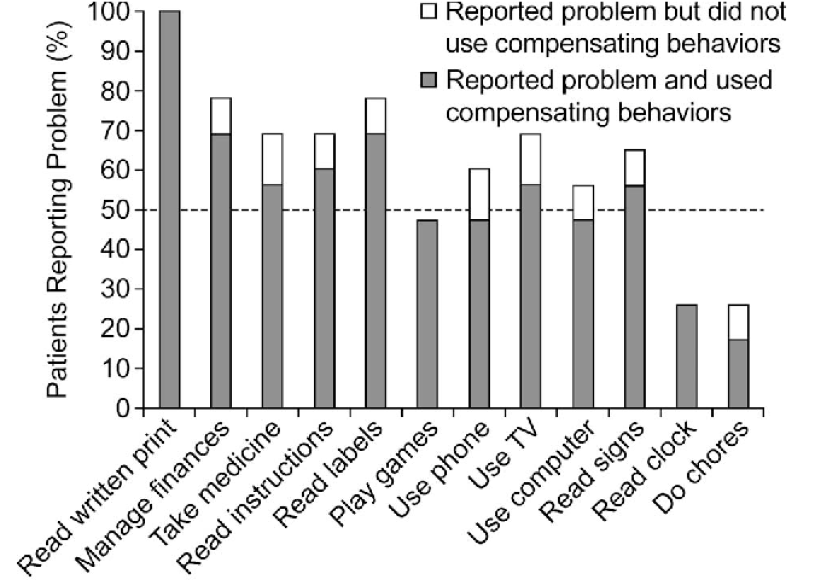

El índice de independencia lectora funcional (FRI1)

El índice de independencia lectora funcional es una medida notificada por el paciente que evalúa la capacidad de una persona con DMAE avanzada seca para leer en una variedad de actividades relacionadas con la lectura.20

Los parámetros del índice de independencia lectora funcional incluyen la lectura de las etiquetas de los frascos de medicamentos o las etiquetas de los alimentos, la lectura necesaria para llevar las finanzas y emitir cheques, y la lectura de palabras en un televisor o un ordenador.20 Esta medida es particularmente importante para las personas con DMAE avanzada seca o AG que a menudo pueden tener déficits visuales que no son captados por la agudeza visual mejor corregida.